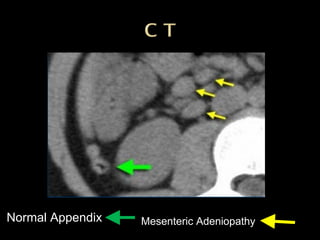

 Mesenteric lymphadenitisis a mimicker of appendicitis.  It is the second most common cause of right lower quadrant pain after appendicitis.  It is defined as a benign self-limiting inflammation of right-sided mesenteric lymph nodes without an identifiable underlying inflammatory process - often in children than in adults..  Diagnosis can only be made confidently when a normal appendix is found, because adenopathy also frequently occurs with appendicitis.  Key finding: Lymphadenopathy with a normal appendix and normal mesenteric fat

Normal Appendix Mesenteric Adeniopathy